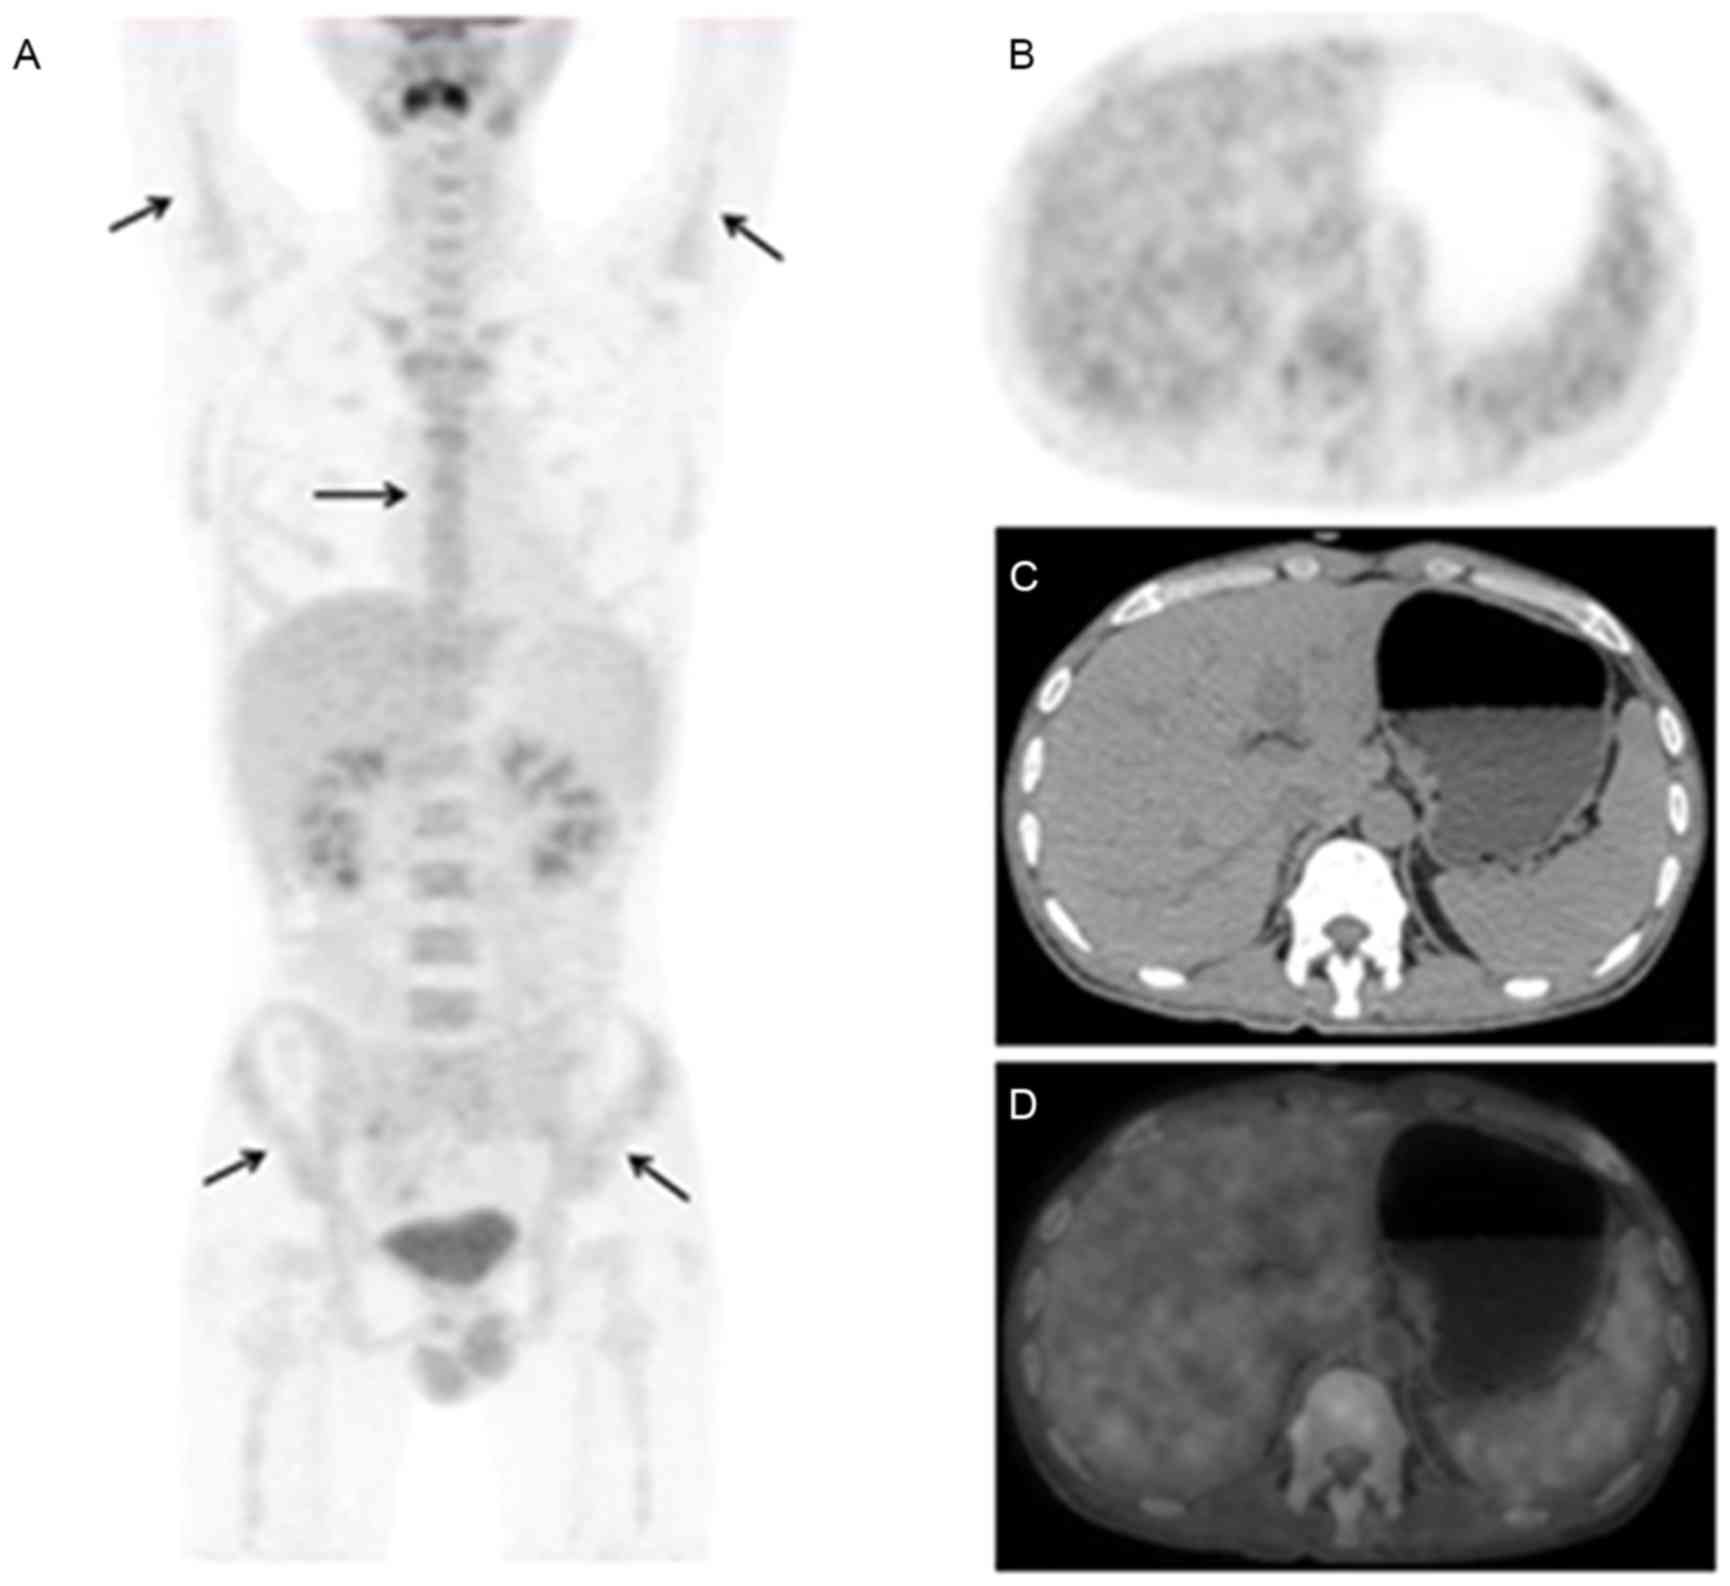

In addition, 1 case presented with marginally increased FDG uptake by the skin of the neck, shoulders and chest, which was caused by the skin rash of the corresponding part (Fig. 1). Another case displayed elevated FDG activity in the right shoulder joint, but the patient had no history of joint diseases. A total of 7 cases presented with effusion on the PET/CT images, including 4 cases with diffuse effusion (pleural, pericardial, abdominal and pelvic effusion; Fig. 2) and 3 cases with local effusion (2 patients with pericardial effusion and 1 patient with pelvic effusion). However, in the present study, no case of liver swelling and/or abnormal glucose metabolism was observed, and the mean SUVmax of the liver was 2.5±0.5 (range, 1.7–3.5).

Figure 1.

A 36-year-old female patient presented with intermittent fever (Tmax of 39.6°C) and rash for almost 1 year. AOSD was diagnosed 10 months ago, and the patient received the therapy of CSs. The rash was worsened after the reduction of CSs, and was widely located in the skin of trunk and limbs. 18F-FDG PET/CT images are presented: (A) MIP, (B) PET, (C) CT, (D) PET/CT, (E) PET, (F) CT, (G) PET/CT. These images indicated diffusely increased FDG uptake by the skin of the neck, shoulders and chest (arrows), with an SUVmax of 3.1. In addition, marginal swelling of the spleen was observed with diffuse FDG uptake. Lymph nodes of the left cervical, bilateral axillary (triangle arrows), lung hilar and abdominal regions were enlarged with mildly increased radioactivity, of which the SUVmax was 2.2. AOSD, adult onset Still's disease; CSs, corticosteroids; 18F-FDG, fluorodeoxyglucose; PET, positron emission tomography; CT, computerized tomography; MIP, maximum intensity projection; SUV, standardized uptake value.